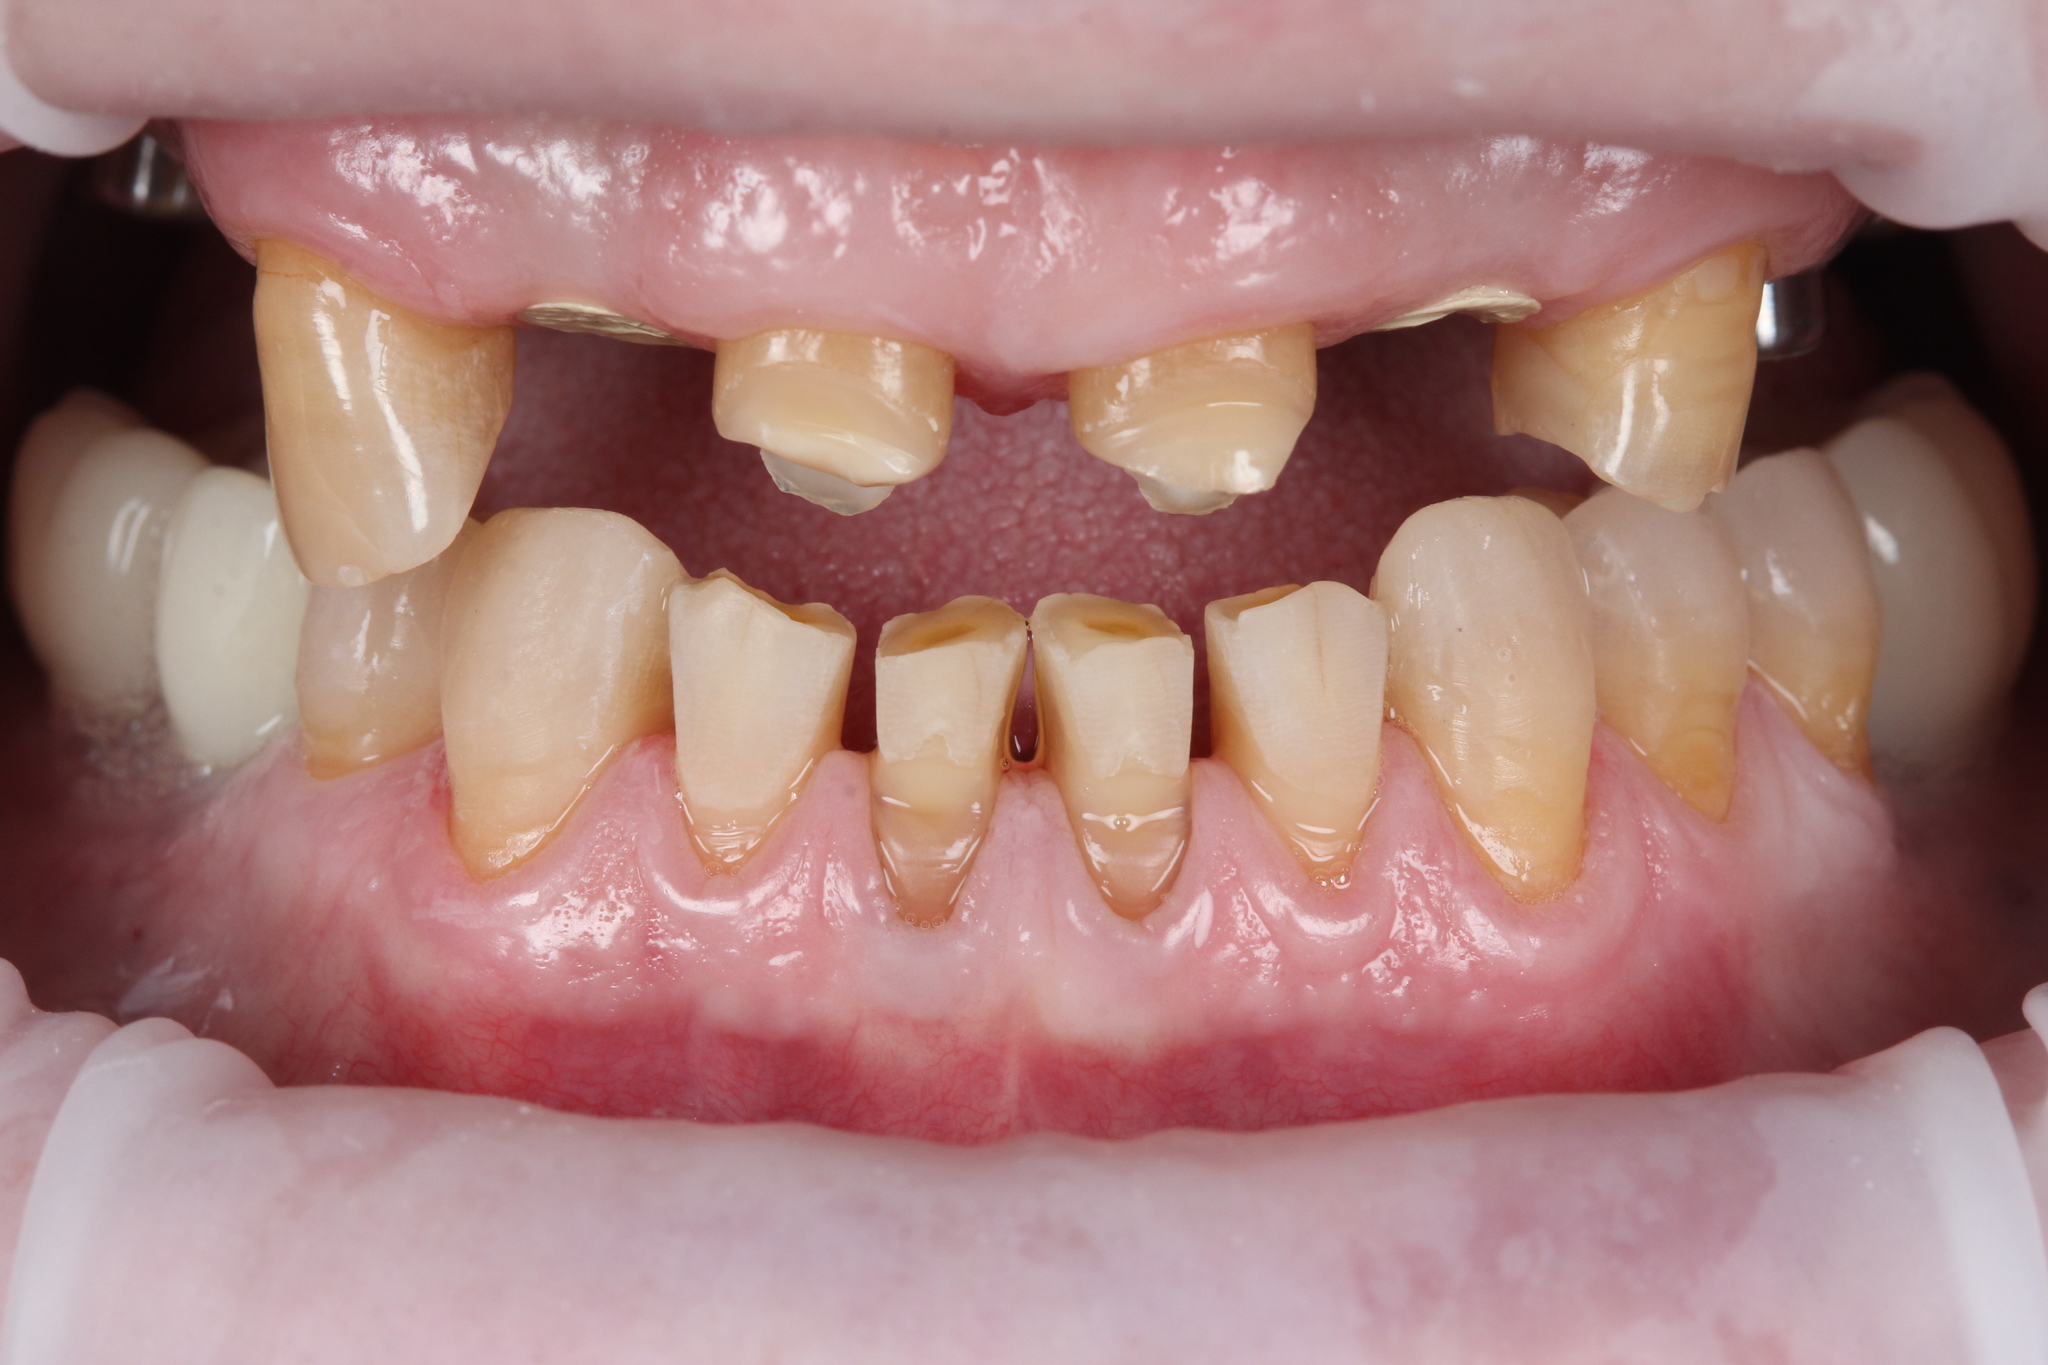

В полости рта ситуация выглядит так:

Отмечается сильная истираемость зубов в связи с длительным отсутсвием полноценного контакта в жевательном отделе.